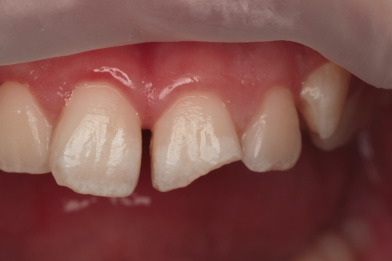

Реставрация верхних резцов с закрытием диастемы

Евсеенкова Дарья Эдуардовна -